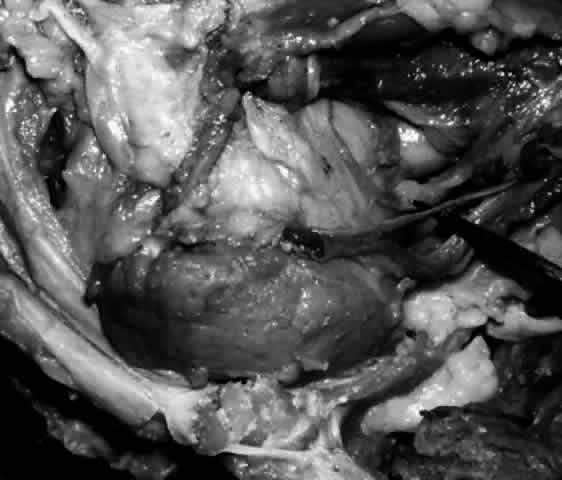

The main lacrimal gland resides in the superotemporal orbit, partially within a shallow bony fossa in the lateral angular process of the frontal bone (fossa glandula lacrimalis). The gland is situated between the eyeball below and the curved orbital wall above, giving it a somewhat compressed and curved shape. It may extend inferiorly to the lateral canthal tendon. The lateral horn of the levator aponeurosis crosses the gland anteriorly, separating it into a larger superior or orbital lobe and a smaller inferior or palpebral lobe (Fig. 2). The division is incomplete because the larger orbital lobe is connected to the smaller palpebral lobe posteriorly by a bridge of glandular tissue, draining tubules, and Müller's muscle, which is attached to the underside of the levator muscle and aponeurosis. The lacrimal gland is surrounded by fibrous tissue that is attached superiorly to the periosteum of the frontal bone and inferiorly to the orbital portion of the zygomatic bone.1

Fig. 2. With the roof and lateral wall of the left orbit removed, this cadaver dissection demonstrates the orbital lobe (black arrow) and the palpebral lobe (white arrow) separated by the lateral horn of the levator aponeurosis (pointer).